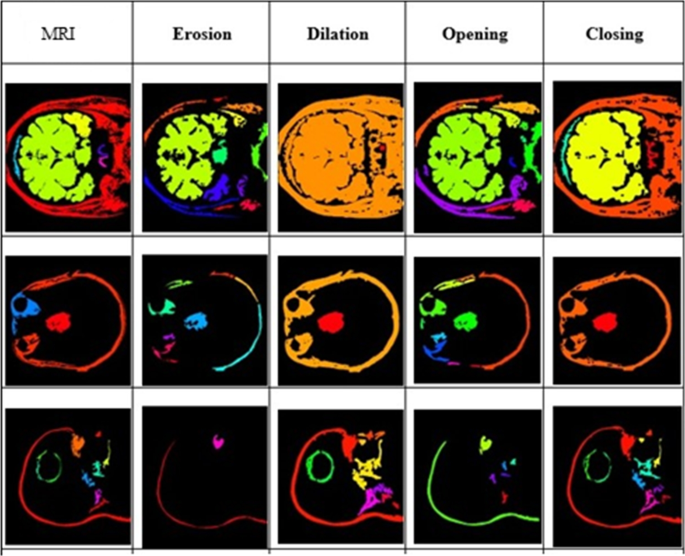

Sophisticated imaging techniques can pinpoint brain tumors. Diagnostic tools include computed tomography (CT or CAT scan) and magnetic resonance imaging (MRI) . Other MRI sequences can help the surgeon plan the resection of the tumor based on the location of the normal nerve pathways of the brain. Intraoperative MRI also is used during surgery to guide tissue biopsies and tumor removal. Magnetic resonance spectroscopy (MRS) is used to examine the tumor's chemical profile and determine the nature of the lesions seen on the MRI. Positron emission tomography (PET scan) can help detect recurring brain tumors.